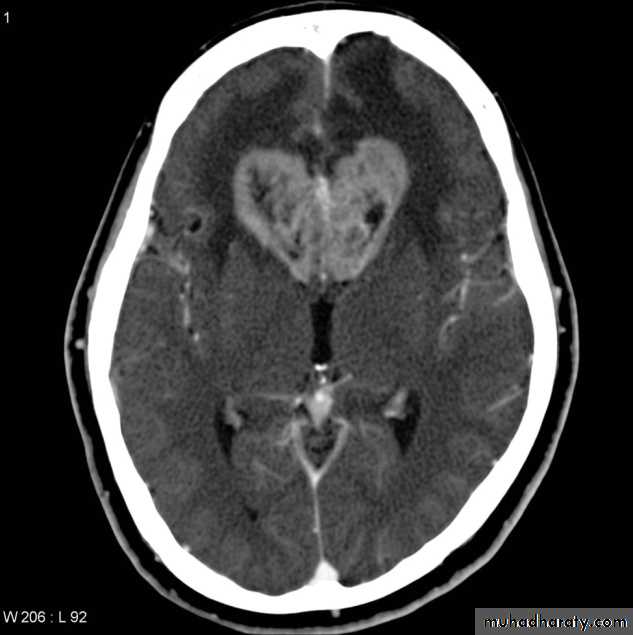

Medullo blastoma

Age incidence between 5-15 Y represent about 35-40 %of PFT

Arise from the midline mainly within or from the roof of the 4 TH ventricle fill the fourth ventricle & seeding via the csf so can seen in the distal part of the spinal canal .

CT finding as well circumscribed lesion heterogeneous in density ,have solid & cystic part , with also scattered calcification little surrounded edema , the solid part is enhance

90 % present with obstructive hydrocephalous at the level of the 4Th V. with dilatation of the lateral V. ( body , frontal , temporal & third ventricle )

40 % of child have secondary metastasis at the time of presentation